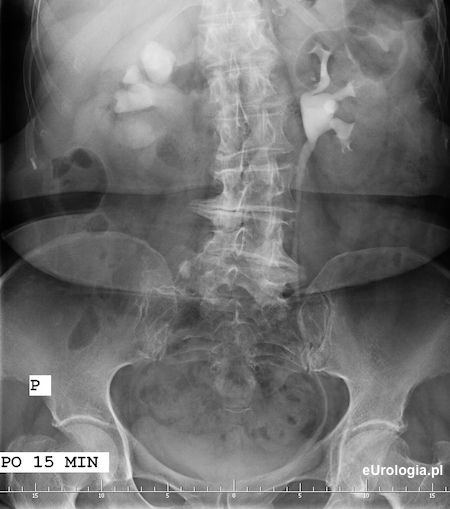

Zdjęcie po 15 minutach po podaniu kontrastu - wodonerczowato poszerzony UKM prawej nerki. Układ kielichowo-miedniczkowy nerk lewej i moczowód lewy na całej długości wypełnione zakontrastowanym moczem

Wodonerczowo poszerzony UKM prawej nerki i poszerzony górny odcinek moczowodu aż do opisywanego na zdjęciu przeglądowym cienia - złóg w moczowodzie.

Zółtą strzałką oznaczono cień wapienny o wymiarach 11x8 mm będący złogiem w górnym odcinku prawego moczowodu.